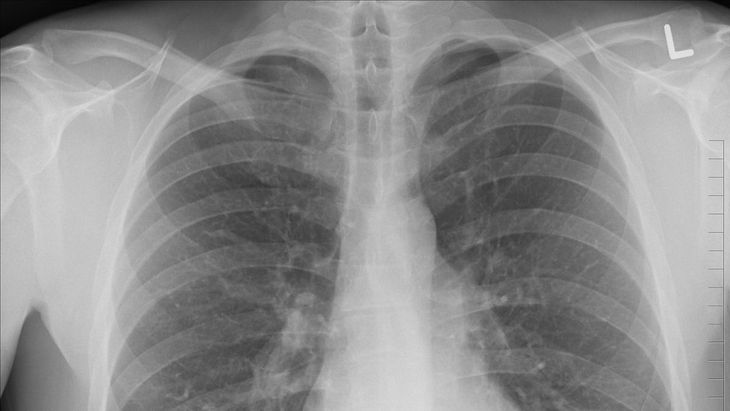

El medicamento comenzó su desarrollo en 2020 y ya está en etapa de ensayos clínicos de fase II, con pacientes humanos. INS018_055 se creó como tratamiento para la fibrosis pulmonar idiopática, una enfermedad crónica que afecta los pulmones. La enfermedad actualmente afecta a millones de personas en el mundo y, de no tratarse correctamente, puede provocar la muerte en un plazo de dos a cinco años.

El estudio actual del fármaco para la fibrosis pulmonar idiopática es un ensayo aleatorizado, doble ciego, controlado con placebo que se lleva a cabo durante 12 semanas en China, pero la startup tiene planes de expandir la población de prueba a Estados Unidos.

Durante el desarrollo de la fase II del ensayo clínico, los especialistas evaluarán la seguridad, tolerabilidad, farmacocinética y eficacia preliminar del fármaco INS018_055 en pacientes con FPI (Fibrosis Pulmonar Idiopática), a quienes se espera pueda ayudar en el tratamiento de esta enfermedad.